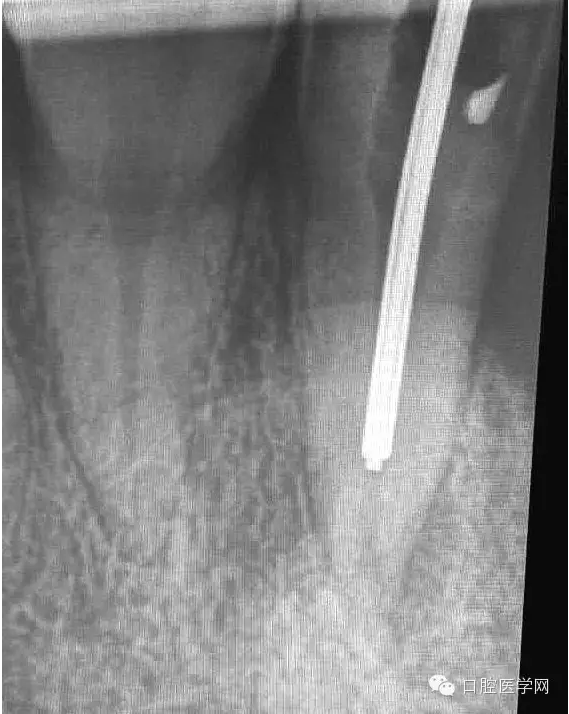

一年前接診的病例,在各級(jí)門(mén)診診所轉(zhuǎn)診三次,不見(jiàn)好轉(zhuǎn)。最后到本院 !觀(guān)察一年以后的效果!

5.待MTA凝固后進(jìn)行熱牙膠充填。